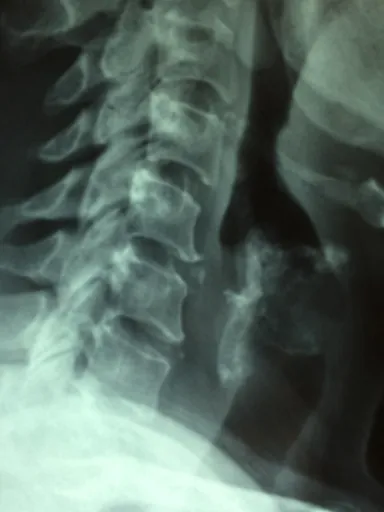

발뒤꿈치 뼈 돌출

흥미로운 점은 족저근막염 환자의 약 70%에서 "발뒤꿈치 뼈 돌출"이 관찰된다는 것입니다. 이는 족저근막이 발뒤꿈치 뼈에 부착되는 부위에 염증이 발생하고, 지속적인 자극으로 인해 뼈 조직이 변형되면서 돌출되는 현상입니다. 이러한 돌출 부위를 직접 눌렀을 때 압통이 느껴지는 경우가 많으며, X-ray 촬영을 통해 확인할 수 있습니다. 하지만 발뒤꿈치 뼈 돌출이 있다고 해서 모두 족저근막염은 아니라는 점! 발뒤꿈치 뼈 돌출은 족저근막염의 결과로 나타나는 현상 중 하나일 뿐, 단독적인 진단 기준으로는 사용되지 않습니다.